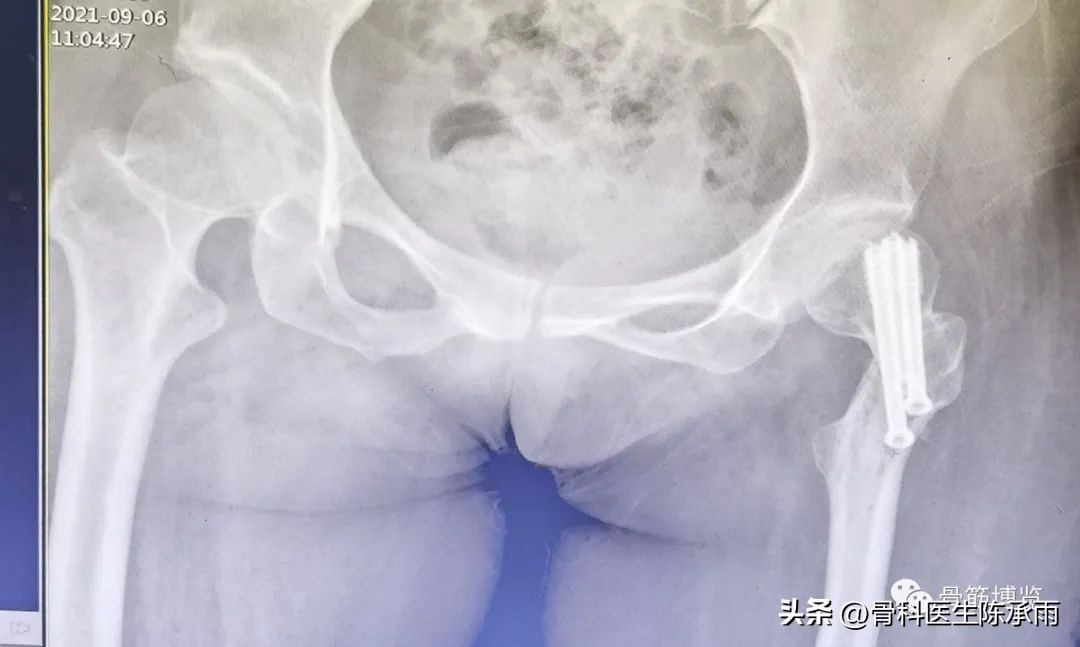

2例

我们这例患者是一位脑瘫患者,患侧肢体短缩细小,股骨颈处及股骨髁上均做过截骨手术,失去了正常的角度,且股骨颈较细。给手术带来不小的难度。

术前尝试闭合复位,效果满意,决定行经皮穿钉,但股骨颈角度不正常,颈部细小,很难容得下3枚直径7.3空心钉,最后1枚空心钉部分切出股骨颈上缘。

术后拍片由于患肢内旋畸形,未显示标准正位